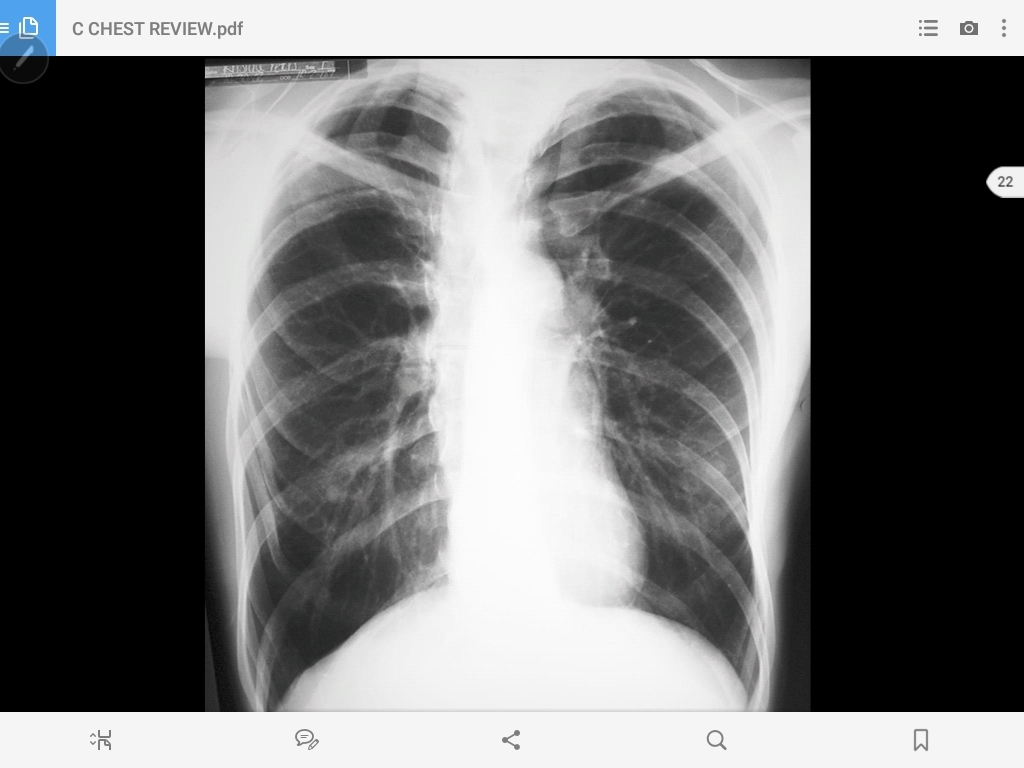

emphysema